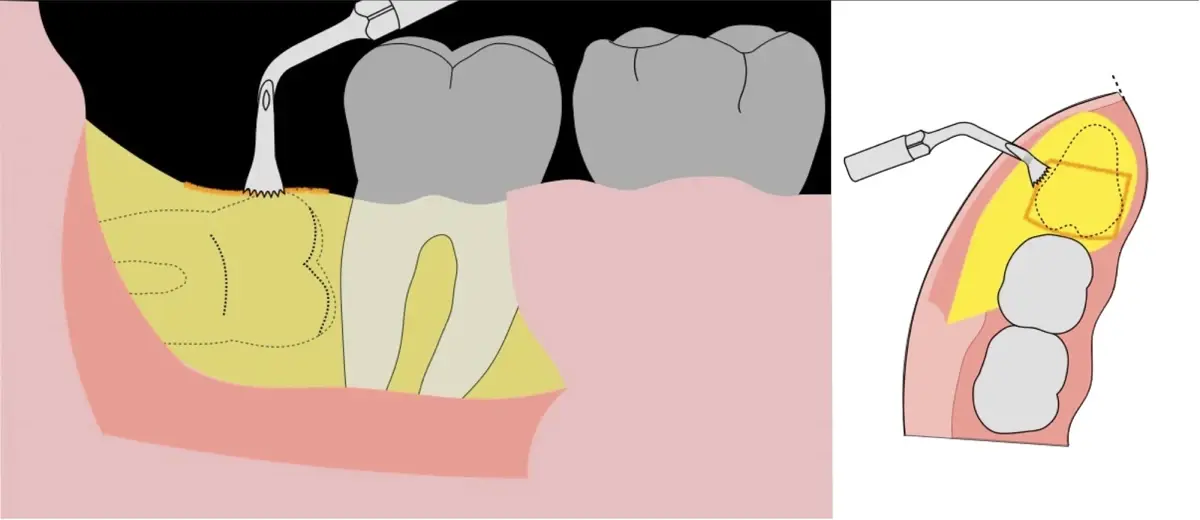

En contraste, el instrumento piezoeléctrico utiliza un corte micrométrico que retira un área de superficie mínima de hueso, y reduce el riesgo de termonecrosis marginal en comparación con las fresas rotatorias convencionales.9 Los micromovimientos mejoran la precisión en el corte y el control táctil, y eliminan las macrovibraciones que se producen con los instrumentos rotatorios.10 Su frecuencia de oscilación es la amplitud de 60-200 μm horizontalmente y de 20-60 μm en sentido vertical, lo que es muy inferior en comparación con las micro sierras oscilantes; por lo tanto, proporciona cortes de osteotomía precisos y seguros. Adicionalmente, posee vibraciones ultrasónicas que descomponen el líquido de irrigación en partículas muy pequeñas (fenómeno de cavitación, que produce un efecto hemostático y así reduce la pérdida de sangre), lo que proporciona una visión clara y sin obstáculos del campo quirúrgico11,12.

El procedimiento se inicia colocando anestesia troncular para bloqueo del nervio dentario inferior y sus ramas. Luego, se establecerá el diseño de acceso según la disposición de la molar a extraer. Para fines didácticos, se explicará cómo se realizaría la extracción de la molar de la Figura 1: se realiza una incisión horizontal a nivel de la zona retromolar hasta llegar a distal de la segunda molar, continuándose con una incisión intrasurcular hasta mesial de la segunda molar, finalizando con una incisión vertical a espesor total hasta llegar a la línea mucogingival (Figura 2).